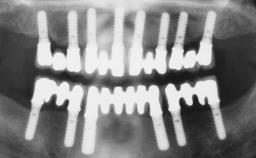

Immediate Loading of Six Implants in the Maxilla and Final Restoration with a Full-Arch CAD/CAM Zirconia FDP

# of Implants 6

Type of Implants One-Piece

Bone Augmentation Horizontal|Simultaneous

Defining Characteristics Fully edentulous upper jaw to be rehabilitated with four or more implants

Modality 6+ implants with immediate loading